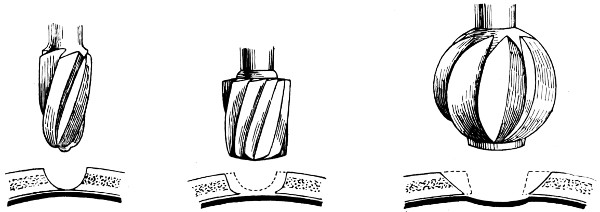

| 7. Hudson’s trephine | 20 |

| 8. The hand-trephine | 21 |

| 9 and 10. The technique of trephining | 22 |

Fig. 7. Hudson’s Trephine. Showing the usual method of using the spiral perforator, spiral follower, and enlarging burr.

Hudson’s trephine is shaped after the style of the carpenter’s brace and is fitted with three cutting heads—the perforator, the follower, and the enlarging burr. It is claimed that injury to the dura and brain is impossible, the instrument becoming automatically locked so soon as the resistance of the internal table is overcome, a thin film of bone being pushed in front of the advancing head. I have had the opportunity of using this instrument, and so far as my experience goes it answers all requirements. Still, I prefer the ordinary hand-trephine so long as it satisfies certain requirements. It must be of simple mechanism and strong, the handle of good size and shaped to fit the hand, the shaft and head so interlocked as to allow of no independent movement, and the hollow head sharply toothed and bevelled externally, in continuity with the teeth, for a distance of half an inch. The bevelling is so arranged that the actual cutting process is only effected during supination of the hand and forearm. The pin of the trephine should not project beyond the cutting edge for a greater distance than about ·2cm. This pin should be readily removable.

Fig. 8. The Hand-trephine.

The pattern which I am accustomed to use is depicted in Fig. 8. The trephines are kept in three sizes—diameter 1⁄2, 1, and 11⁄2 inches. The intermediate size is used for ordinary trephining, the small one for the formation of the osteoplastic flap, the large for the removal of a disk of bone which includes within its circumference the area involved in some depressed and punctured fractures (see p. 133).

Fig. 9.

Fig. 10.

To show the technique of Trephining. Fig. 9 illustrates the act of trephining for cerebellar exposure. Fig. 10 shows a trephine-disk to one side of a depressed fracture.

The site of trephining may be fixed by the introduction of a bradawl through the scalp, so indenting the external table that the spot can be verified on turning down the scalp-flap. The pin of the trephine is there applied, and the trephine directed at right angles to[23] the surface of the skull, or at that angle which is suited to the region attacked. The pin is discarded when a sufficient groove has been attained. The trephine must be kept under perfect control, muscular effort only being required during the act of supination.

Fig. 11. Horsley’s Disk or Bone Elevator.

Fig. 12. Horsley’s Dural Separator.

Fig. 13. Keen-Hoffmann’s Craniectomy Forceps.

The firm nature of the external table will be readily appreciated; so soon as this resistance is overcome the trephine will be felt to be cutting its way through a softer structure, whilst the increased bone-dust and venous oozing will make it evident that the instrument is biting its way through the diploic tissue. Greater resistance is again encountered on meeting the internal table, warning the operator that the time has come when greater care must be exercised. The bone-dust must be wiped away, the teeth of the trephine cleansed with nail-brush or sponge, and the depth of the groove estimated. The groove should be of the same depth throughout its circumference, or of that depth which is suited to the part involved.

The readiness of the disk for removal is best demonstrated[24] by digital pressure. When it gives to that pressure, whether in whole or in part, the elevator may be applied and the fragment removed.

In the temporal and cerebellar regions special care is required by reason of the absence of diploic tissue.

It is impossible to lay too much stress on the necessity of avoiding injury to underlying dura and meningeal vessels. Injury to these structures not infrequently upsets the whole plan of campaign.